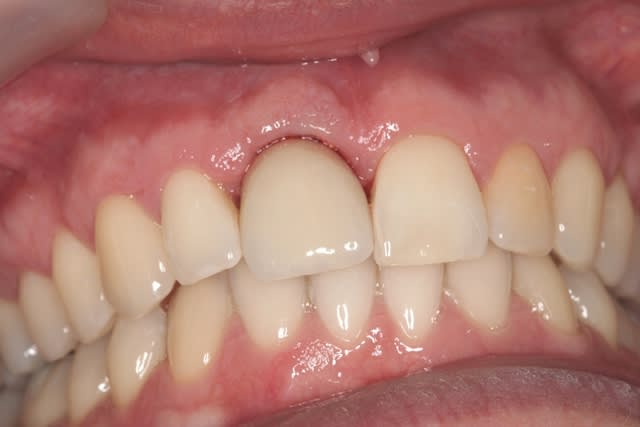

çà manque un peu de cas en ce moment...alors en voilà un ptit au passage...

11 avec résorption interne

EII avec MCI sur du dentium (4.5/14) comblement du gap vestibulaire avec du kasios tcp (très constant dans les résultats...et très économique)

pas de photos de chir par contre...j'ai du les effacer par erreur...grrrr...

la prothèse d'usage a été réalisée par ma petite associée...mais j'étais là pour superviser et faire quelques photos...;-)